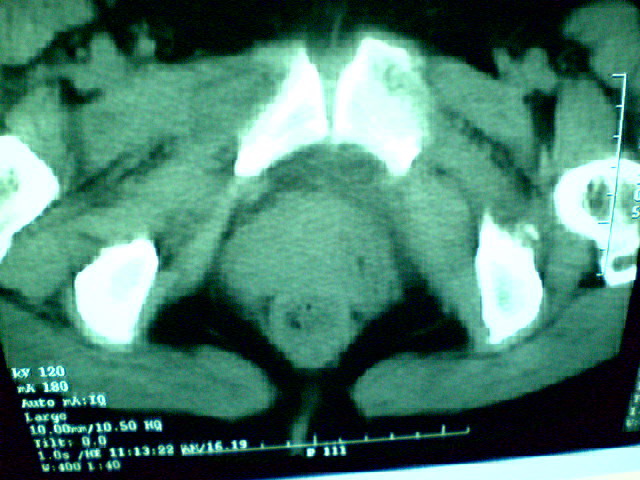

f 60y,b超提示脂肪瘤.[img][/img]

右侧附件囊性畸胎瘤,三种组织均见.

右侧附件囊性畸胎瘤.

那个高密度灶形状好象牙齿。典型,收藏了

脂肪密度肿块,内可见团块状影,典型皮样囊肿

的确比较典型的畸胎瘤!不过,应该确切的说是盆腔畸胎瘤,右侧附件来源的可能性比较大。

有钙化,畸胎瘤